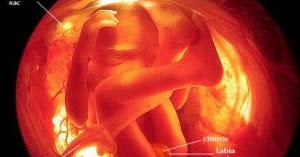

Pertumbuhan rahim ke depan akan mengubah keseimbangan tubuh ibu. Dalam sebuah video yang ia berikan judul my wife´s belly movement. Ciri khusus tahapan ini adalah terlihatnya fetus menyerupai manusia, dengan wajah, kedua tangan dan kakinya. Anda mungkin akan dapat mengingat setiap detik perkara yang berlaku sebelum, semasa dan selepas melahirkan si kecil. Kondisi ini bagian normal dari perkembangan janin.

Ternyata ada banyak yang bisa mereka lakukan ya! Sebagian orang percaya, jika dengan memperdengarkan musik, terutama musik klasik. Pada perkembangan bayi 5 bulan di dalam perut, ibu akan mulai merasakan gerakan si kecil dalam rahim, yang seakan ingin memberikan tanda ketidaksabarannya untuk segera lahir ke dunia dan melihat raut wajah ibunya. Pertumbuhan bayi dalam rahim usia 2 minggu. Ciri khusus tahapan ini adalah terlihatnya fetus menyerupai manusia, dengan wajah, kedua tangan dan kakinya.

Banyak yang terjadi dalam fase ini, mulai dari perkembangan janin sampai perubahan tubuh ibu dengan perut yang semakin membesar. Pembuahan terjadi sekitar dua minggu setelah awal mulainya masa haid. Usg pada hari selasa 30 september 2014 usia kandungan 13 minggu 1 hari. Selain bisa menendang perut si ibu, ternyata bayi bisa cegukan, bernapas dan buang air kecil di rahim. Saat perkembangan janin 5 bulan, bayi ibu sudah bisa mendengar.